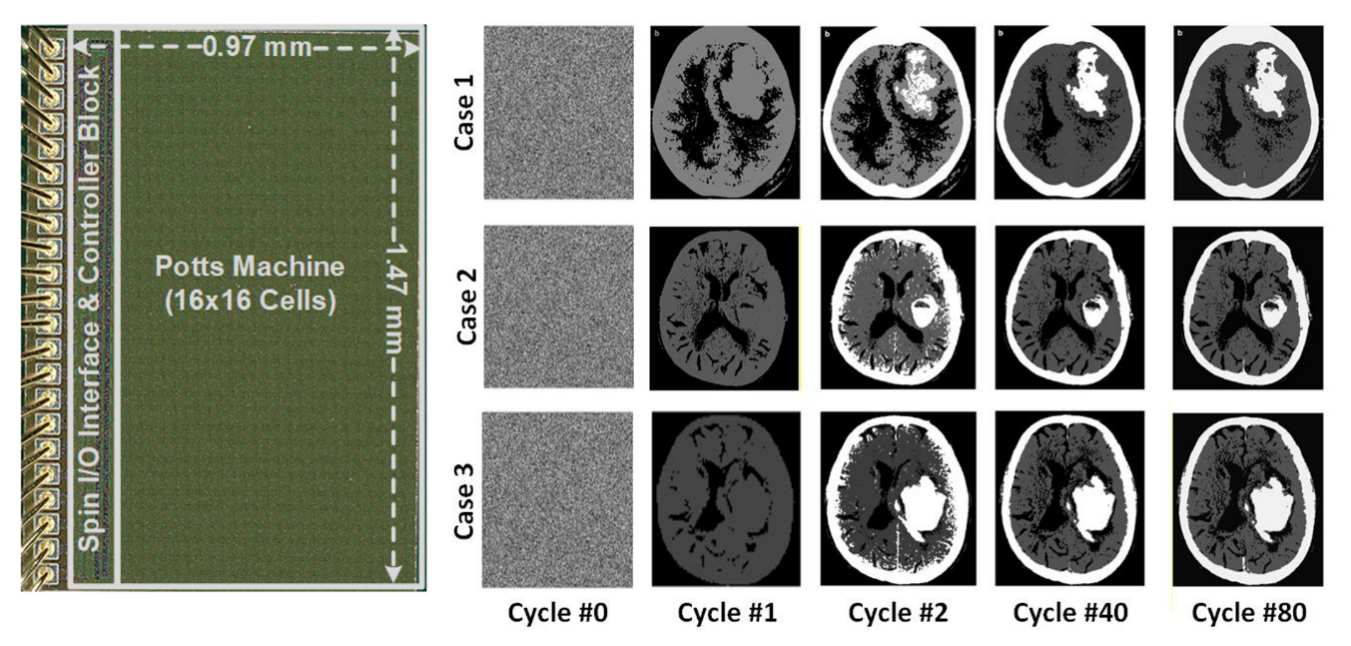

波茨机芯片的显微图及其在CT图像聚类中的应用。